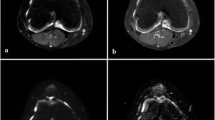

Conventional MRI assessment

Patients were divided in two groups (MRI-inactive and -active JIA) based on the presence or absence of synovial inflammation on MRI as defined by JAMRIS in which measurements of synovial membrane thickness are carried out in six knee compartments, as described before in detail [7]. A total score of 0 for synovial hypertrophy corresponds to no synovial inflammation (MRI-inactive JIA); a score of 1 or higher for synovial hypertrophy is perceived as synovial inflammation (MRI-active JIA). Figure 1 demonstrates representative MR images of a patient with MRI-inactive JIA and a patient with MRI-active JIA. All MRIs were scored by one experienced reader (RH, 7 years experience with MR imaging in the knee) who was blinded for clinical history, current symptoms and clinical examination of the patients.

MRI example of two patients using a sagittal T1 pre- and post-contrast image and an axial T1 SPIR post-contrast image. MRI-active disease: the upper row represents an 11-year old boy with JIA who had synovial hypertrophy in multiple knee compartments, resulting in a total JAMRIS (Juvenile Arthritis MRI Scoring System) synovial hypertrophy (SH) score of 8. Note the enhancing and thickened synovial membrane in both the sagittal T1 post-contrast slice and the axial T1 SPIR. MRI-inactive disease: the lower row represents a 12-year old girl with JIA with no synovial hypertrophy in the knee (JAMRIS SH 0)

The median age of the children was 13.1 years (IQR 11.4–15.7 years) and 25 of 35 patients (71%) were female. Patient characteristics and disease activity parameters of MRI-inactive and -active JIA patients are shown in Table 2. No statistically significant differences between the two groups were observed regarding those clinical parameters. In active patients, the median number of ROIs per patient was 5 (IQR 5-5); for inactive JIA, the median number of drawn ROIs per patient was 4 (IQR 3-5). In total, 151 ROIs were drawn. An imaging example of ROIs in an MRI-active patient and MRI-inactive patient is shown in Fig. 3.

Example of a T1 dynamic contrast-enhanced image and parametric maps (maximum enhancement (ME) and apparent diffusion coefficient (ADC)) of an MRI-active JIA patient (upper row) and MRI-inactive JIA patient (lower row) with demonstration of region of interest (ROI) placement. Arrows point to the ROIs. ROIs were placed in synovial tissue. Joint effusion (if present) was not included in the ROI, as can be seen in the T1 DCE image of the 11-year old boy with MRI-active JIA